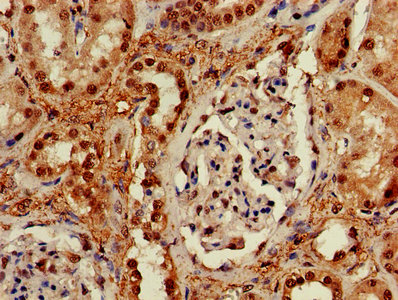

CSB-PA897459LA01HU

IHC image of CSB-PA897459LA01HU diluted at 1:600 and staining in paraffin-embedded human kidney tissue performed on a Leica BondTM system. After dewaxing and hydration, antigen retrieval was mediated by high pressure in a citrate buffer (pH 6.0). Section was blocked with 10% normal goat serum 30min at RT. Then primary antibody (1% BSA) was incubated at 4°C overnight. The primary is detected by a biotinylated secondary antibody and visualized using an HRP conjugated SP system.